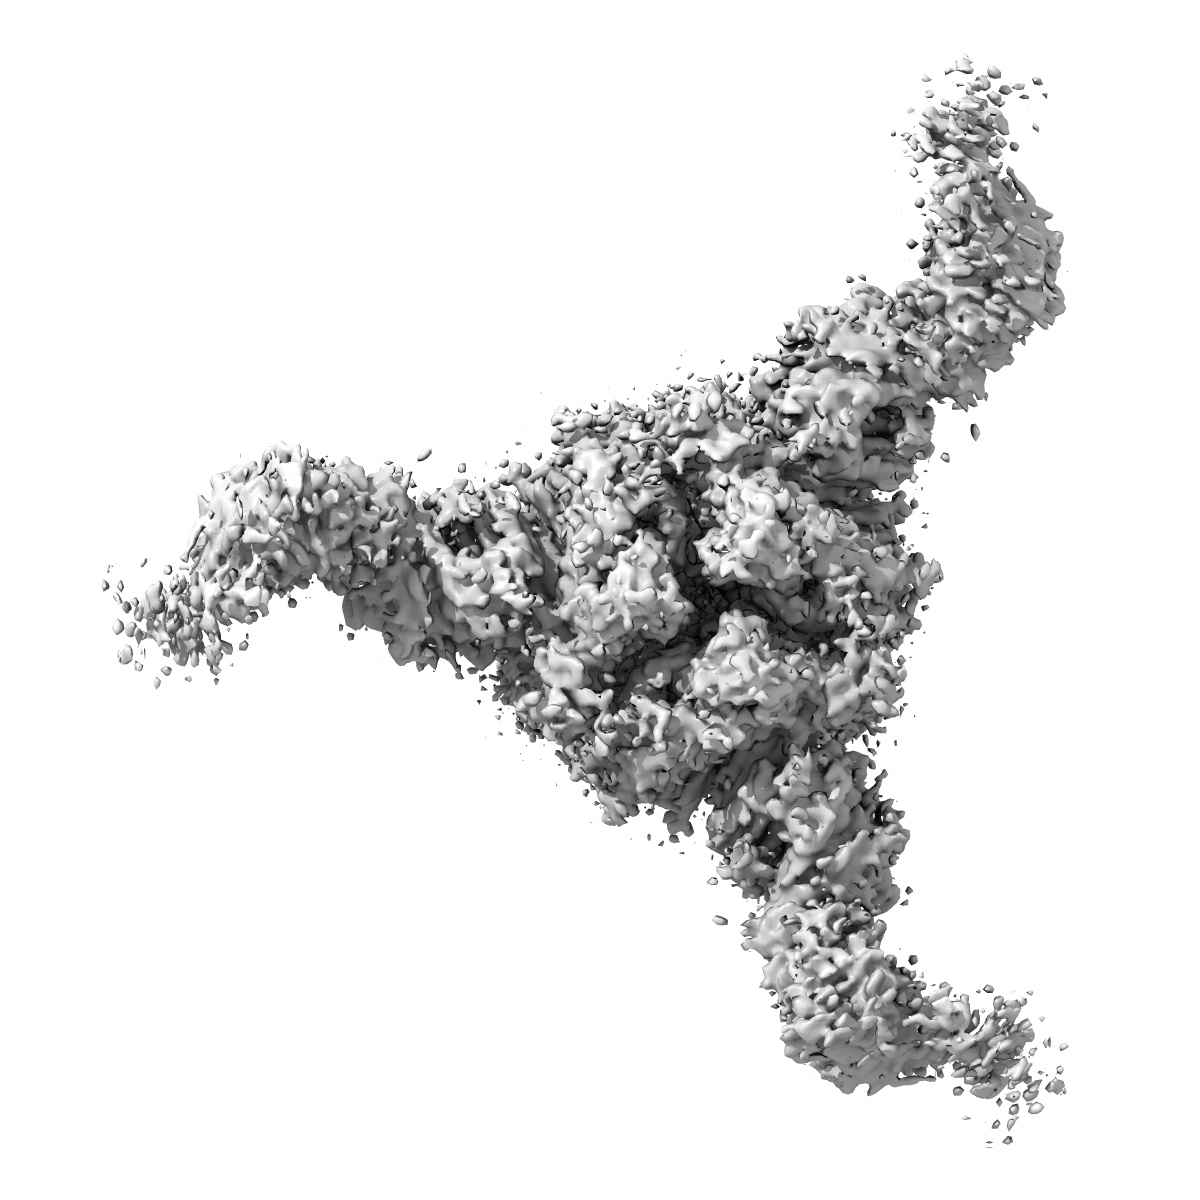

Cryo-EM structure of SARS-CoV-2 spike protein in complex with neutralizing human antibody WRAIR-2008

Single-particle3.23 Å

Sample: SARS-CoV-2 spike protein with WRAIR-2008 Fab

First-generation N-terminal domain supersite public antibodies retain activity against Omicron-derived lineages and protect mice against Omicron BA.5 challenge.